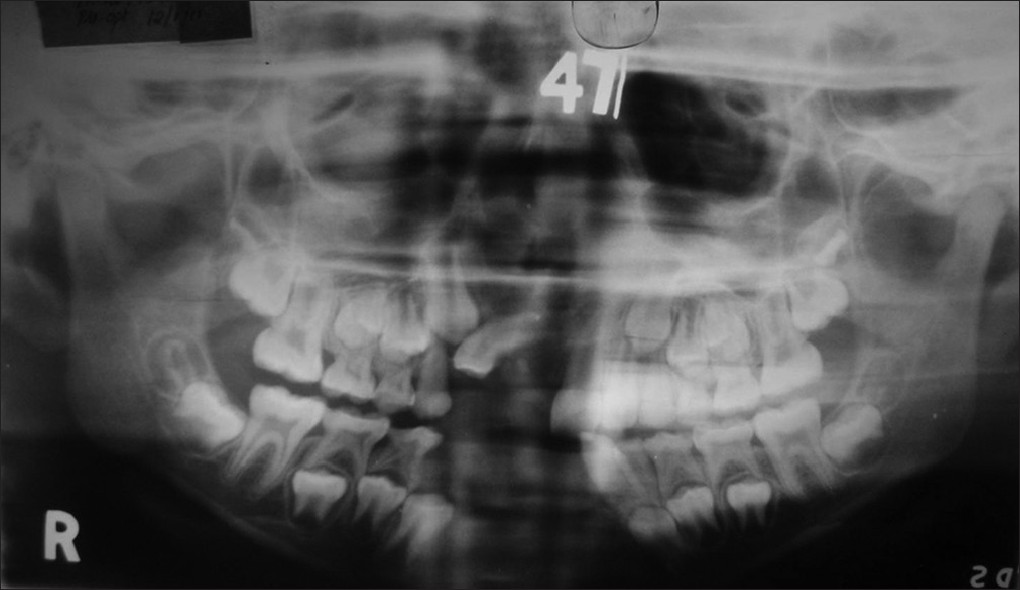

Conservative treatment of keratocyst: A follow-up study |

p. 169 |

Vibha Singh, Shadab Mohammad, Nimisha Singh, Somdipto Das DOI:10.4103/2278-9626.112322 Objective: Odontogenic keratocyst (OKC) is a cyst of tooth origin with an aggressive clinical behavior, including a high recurrence rate. The OKC is well known for its tendency to recur, potential aggressive behavior and defined histopathological feature. The aim of our study is to report the outcome of conservative treatment protocol for OKC. Materials and Methods: A retrospective chart review was undertaken of all cases of OKC treated at Department of Oral and Maxillofacial Surgery, KGMU, Lucknow between 2007 and 2009. A total of 35 cases of cystic lesion were identified, which were treated by one group of surgeons. On histopathological examination 17 patients out of 35 were diagnosed as OKC. We have treated all the patients of OKC with surgical curettage followed by iodoform dressing. There was only one recurrence reported, which was further treated by resection. Clinical features and various treatment modalities of OKC are discussed. Conclusions: Enucleation followed by open packing can be used as a choice of treatment with low recurrence rate for the large keratocystic lesions. The patient should have periodic radiographic and clinical examination. In the cases of the recurrence, lesion should be treated by resection and reconstruction |